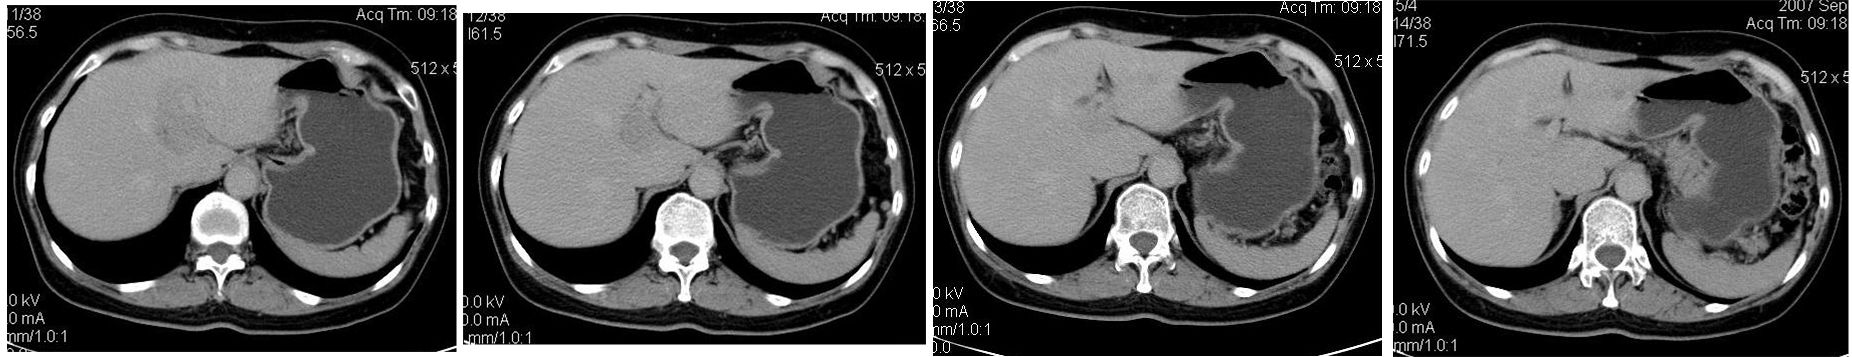

患者,女,65岁,住院准备甲状腺腺瘤用术,术前常规发现肝脏占位,ct增强扫描。

平扫